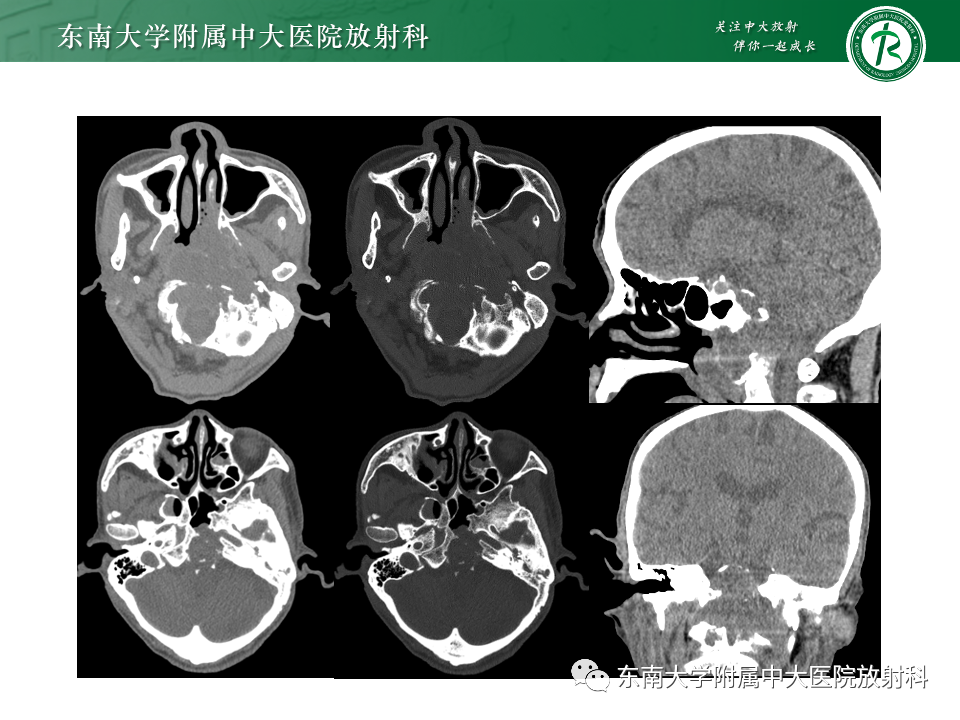

病例1:脊索瘤

病例2:弥漫大B细胞淋巴瘤

病例3:侵袭性垂体瘤

病例4:鼻咽癌